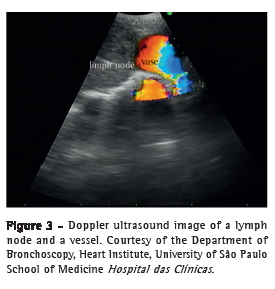

The device has a convex ultrasound transducer (probe) integrated into the distal end, with a 60° scanning angle. The systems provide different frequencies (5-12 MHz), there being variation among the brands available. Because lower frequencies translate to greater tissue scanning depth, the use of higher frequencies results in better image quality at more superficial layers. The Doppler function of the system allows identification of vascular structures, providing greater safety during aspiration of mediastinal lesions or enlarged mediastinal lymph nodes. The picture-in-picture feature of the bronchoscope processor allows the bronchoscopic and ultrasound images to be displayed side by side on the same screen.(6)

The device should be passed through the larynx with caution, given that the bronchoscopic view is oblique and the ultrasound probe is located posteriorly to that view. Subsequently, ultrasound imaging of the lesion that will be diagnosed or of the first lymph node station that will be aspirated should be performed. After the tip of the device touches the tracheobronchial wall, the balloon should be inflated with distilled water so that the ultrasound probe is flat against the tracheal or bronchial wall, and the best ultrasound window to the lesion or lymph node should be found before aspiration. A 3- or 4-cm ultrasound depth is sufficient for the purpose of the examination. At this point, the gain, contrast, and brightness of the ultrasound image can be adjusted to obtain the highest resolution image of the lesion or structure. Doppler is recommended to differentiate between solid structures (lymph node or tumor) and vascular structures (Figure 3).(6)